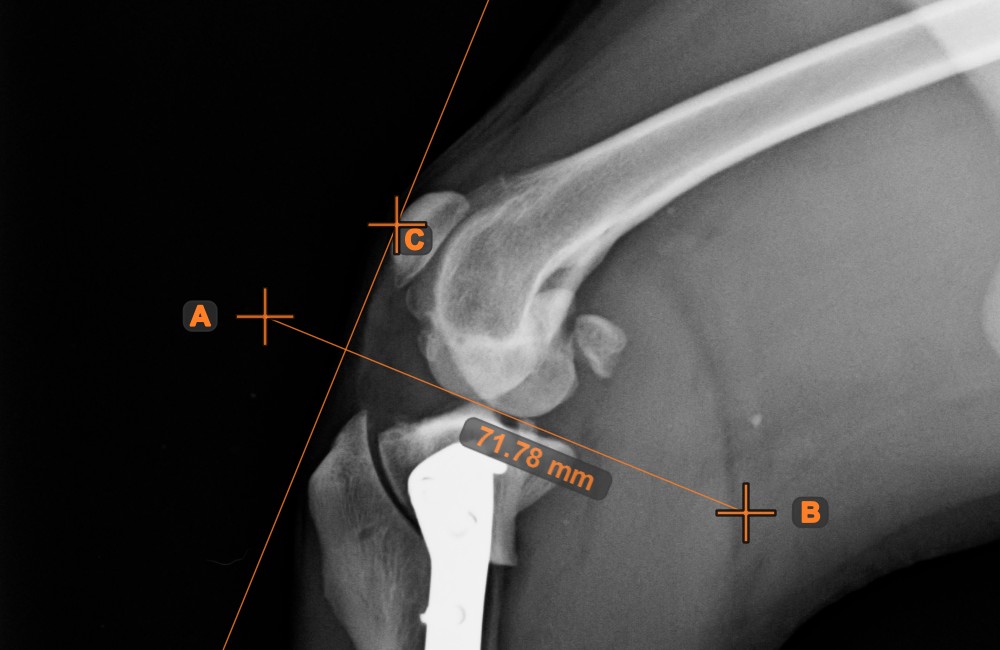

Angle of Lines¶

Select the tool from the left toolbar and assign it to one of the available mouse buttons. Start by selecting the first line from the ones already drawn on the scene, or place the start and end points to create the line. Follow the same steps for the second line of the measurement. The angle between the two lines will be automatically calculated.

Modify the start and end points of both lines by using the Select/Move Item tool. The angle between the two lines will be automatically recalculated.